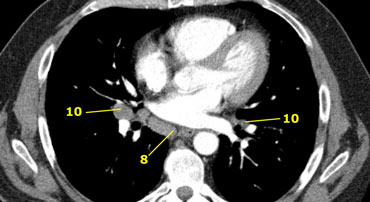

Axial CT anatomy

Images by Dr. Aurelia Fairise of the Institut de Cancérologie de Lorraine in Nancy.

8. Cạnh thực quản

10. Rốn phổi

8. Hạch cạnh thực quản

Hạch ở dưới carina và kéo dài theo chiều dọc đến cơ hoành.

10. Hạch rốn phổi

Hạch gần thùy phổi, xa màng phổi trung thất và nằm gần phế quản trung gian bên phải.

Hạch 10-14 thuộc nhóm N1 vì không nằm trong trung thất.